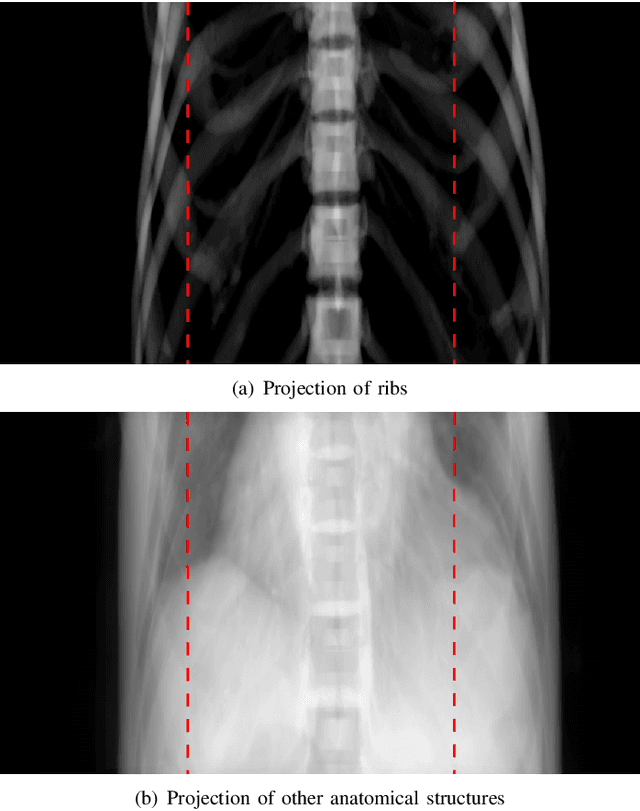

Abstract:Cone-beam computed tomography (CBCT) is widely used in interventional surgeries and radiation oncology. Due to the limited size of flat-panel detectors, anatomical structures might be missing outside the limited field-of-view (FOV), which restricts the clinical applications of CBCT systems. Recently, deep learning methods have been proposed to extend the FOV for multi-slice CT systems. However, in mobile CBCT system with a smaller FOV size, projection data is severely truncated and it is challenging for a network to restore all missing structures outside the FOV. In some applications, only certain structures outside the FOV are of interest, e.g., ribs in needle path planning for liver/lung cancer diagnosis. Therefore, a task-specific data preparation method is proposed in this work, which automatically let the network focus on structures of interest instead of all the structures. Our preliminary experiment shows that Pix2pixGAN with a conventional training has the risk to reconstruct false positive and false negative rib structures from severely truncated CBCT data, whereas Pix2pixGAN with the proposed task-specific training can reconstruct all the ribs reliably. The proposed method is promising to empower CBCT with more clinical applications.